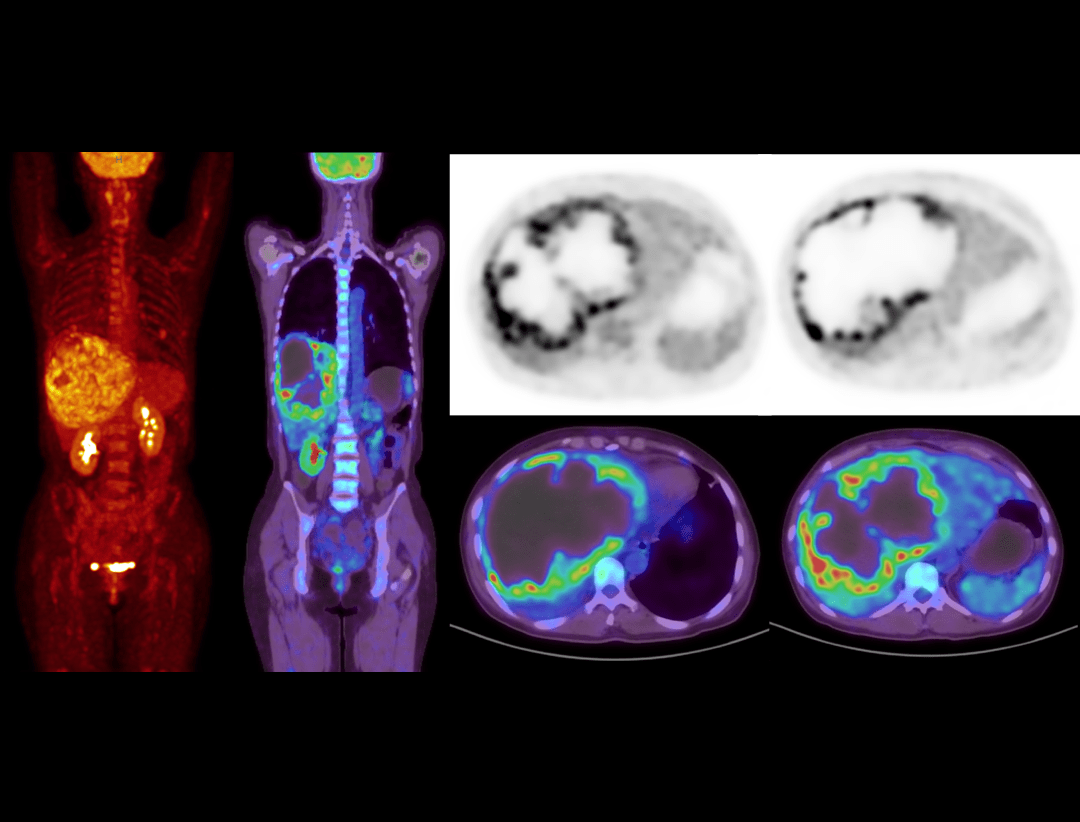

Galerie clinică

Scanare întregului corp în 8 minute

Imagistică PET/CT pentru pacienți cu indice BMI de 40,3

Scanare FDG la 0,05 mCi/kg

Detectarea leziunilor mici de 2,2 mm

Imagistică cerebrală de înaltă rezoluție

Limfom gastric evaluat prin FDG